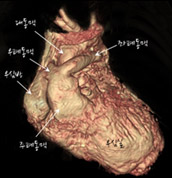

CT로 본 대동맥근 전위술의 수술 전후 모습

- 정면에서 본 모습

[사진4] 수술 전 -

[사진5] 수술 후

수술 전에 대동맥이 심장 앞쪽에서 기시하는 것을 관찰할 수 있습니다. 수술 후 대동맥 자체가 후방으로 이동했고 폐동맥으로 lecompte maneuver를 해서 대동맥 앞으로 옮기고 좌,우폐동맥이 팔을 벌린 모양을 하고 있습니다. 폐동맥이 이전의 대동맥 자리에 위치해 전방의 흉골에 덜 눌리는 모양입니다.